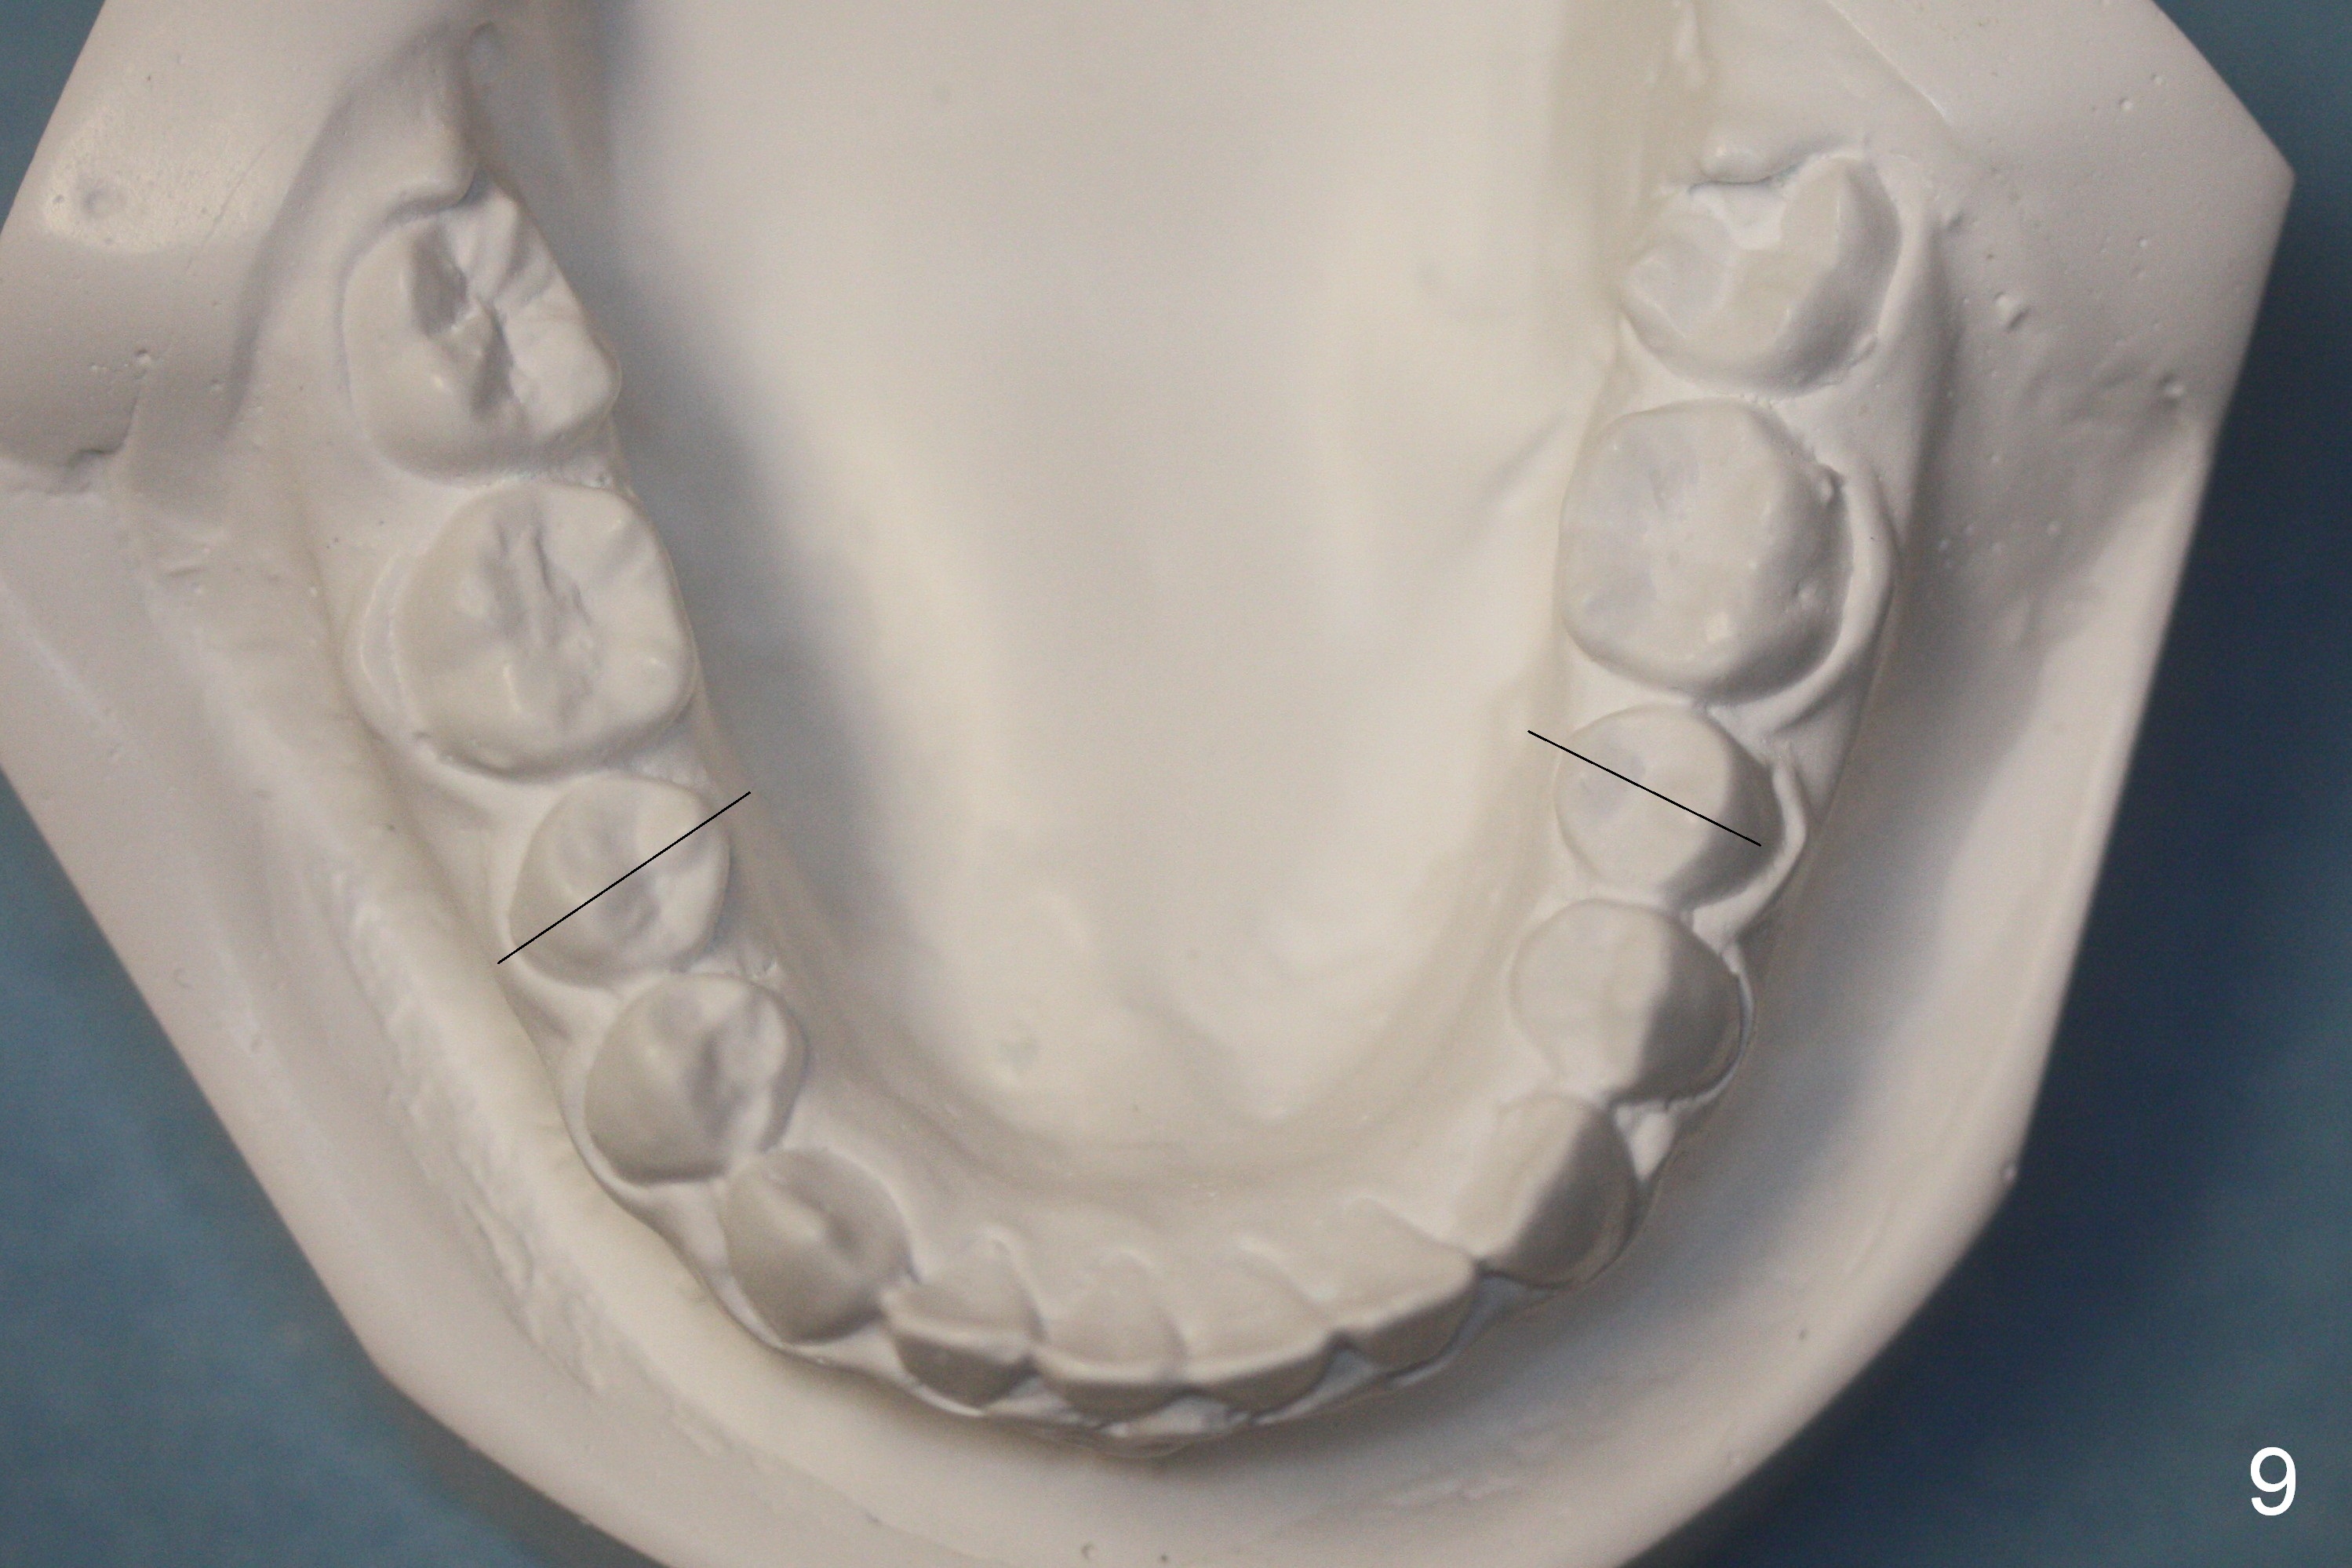

Crowding & Rotation

Joshua, 11 years old, has dental crowding (Fig.1), particularly in the lower arch (Fig.3) with molar Class I relationship (Fig.2). The lower 5s rotate (Fig.2 black lines), which are corrected with power chains (Fig.4,5) after bracketing and placing .012" niti wires (Fig.6).

The orthodontic treatment finishes in 9 months. Incisor overbite improves (compare Fig.7,8 (lingual view of the anterior arches; arrowheads: upper palatal gingival margin)). The rotation of the lower 2nd bicuspids (Fig.9 black lines, as compared to those in Fig.3) and the crowding of the lower anterior teeth (Fig.9) also improves. Two years later, the latter relapses.